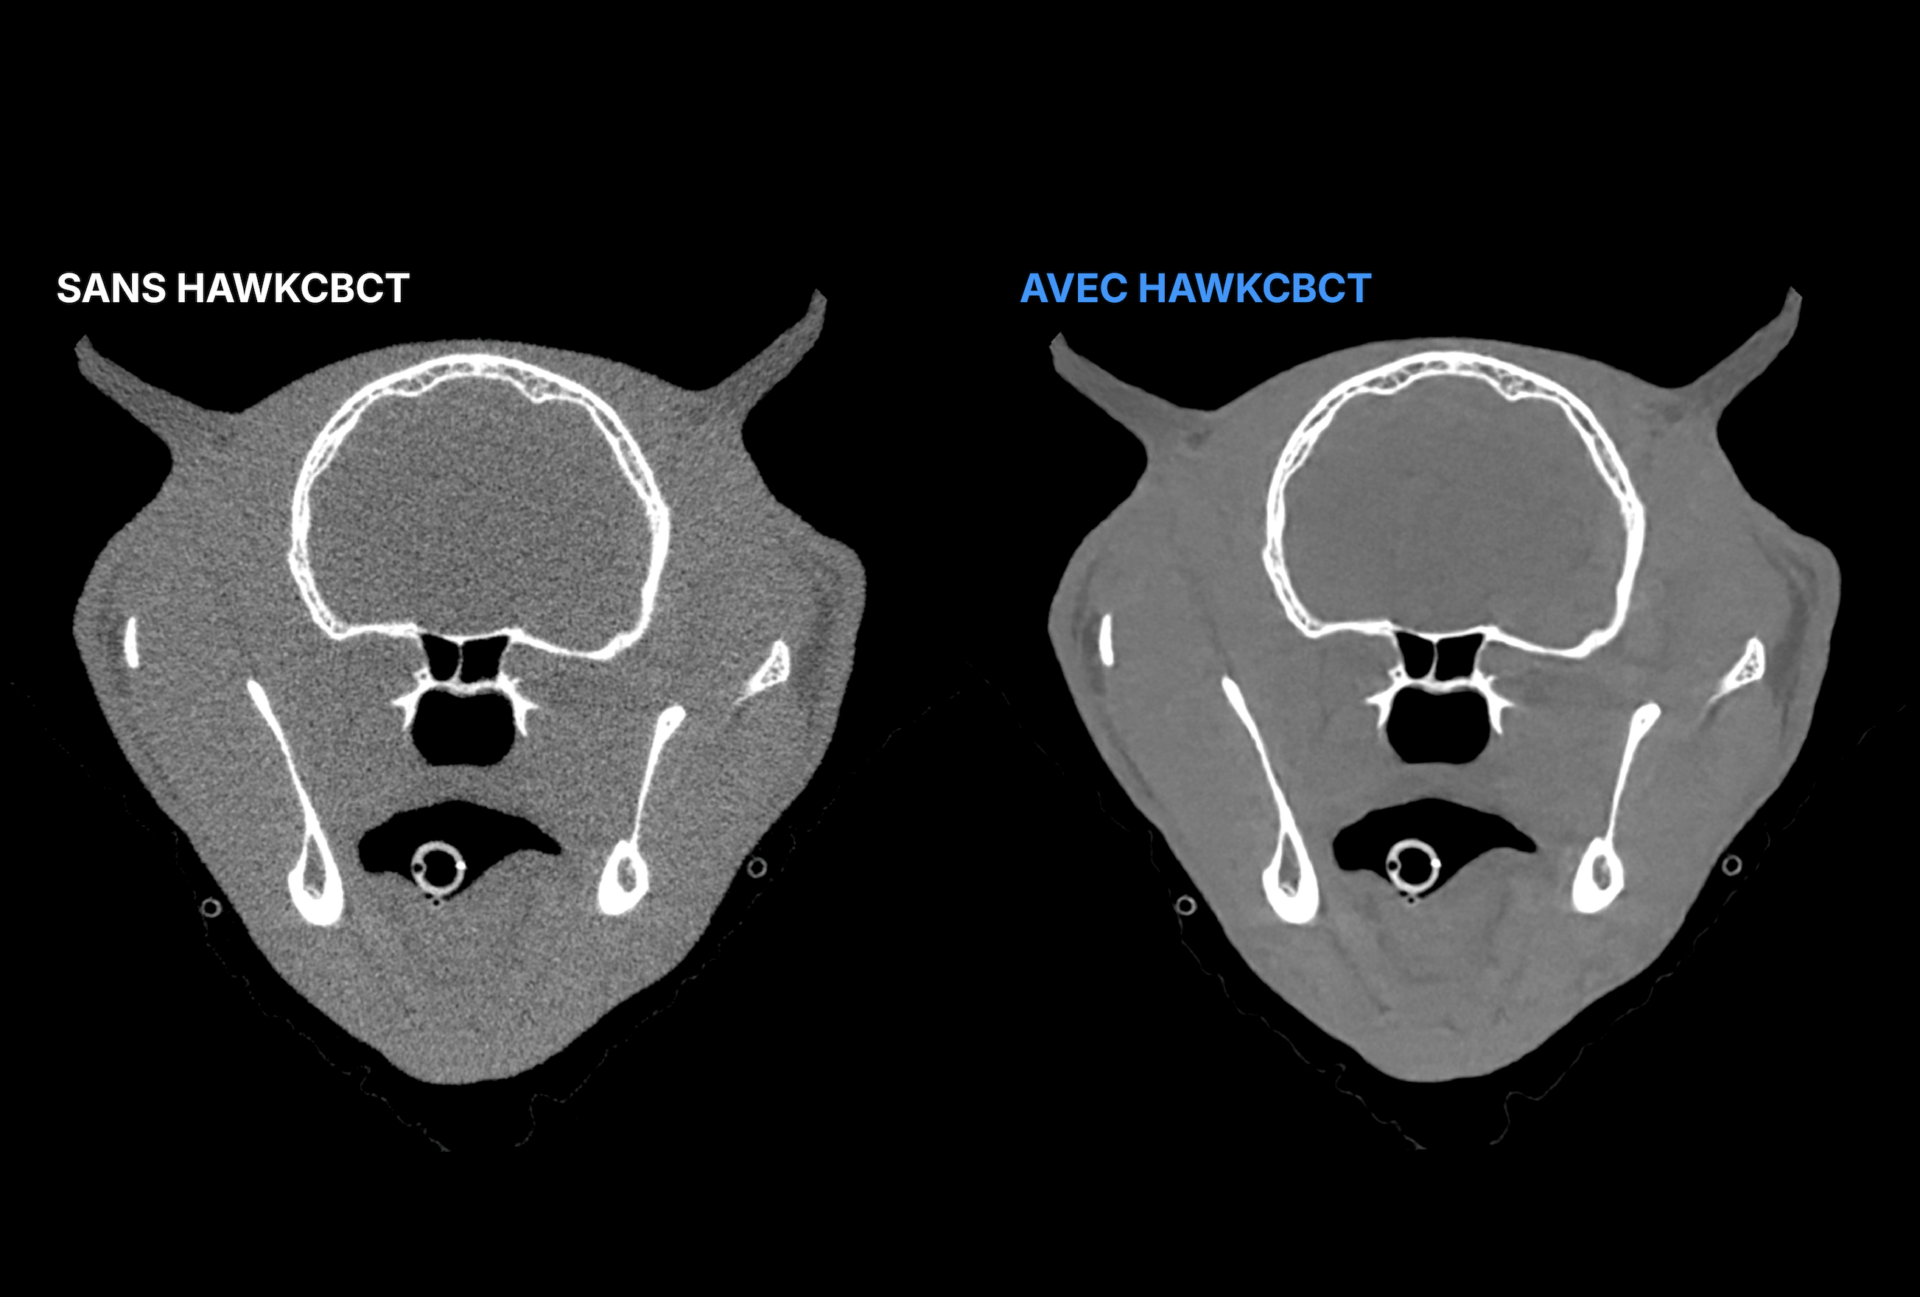

En réduisant le bruit et en comblant l’écart avec la qualité d’image du CT, il offre des scans plus nets et un niveau supérieur de constance d’image. Son amélioration avancée renforce la visualisation des tissus mous, donnant aux équipes vétérinaires une visibilité plus précise là où elle compte le plus. Intégré de manière fluide aux workflows existants, HawkCBCT aide les cliniques à gagner du temps, à fluidifier la lecture des images et à extraire davantage de valeur de chaque scan. Conçu exclusivement pour les vétérinaires et entraîné sur des données animales, il transforme le CBCT en un outil d’imagerie plus puissant et plus fiable.